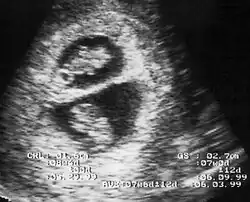

Diagnosis

By performing an obstetric ultrasound at a gestational age of 10–14 weeks, monochorionic-diamniotic twins are discerned from dichorionic twins. The presence of a "T-sign" at the inter-twin membrane-placental junction is indicative of monochorionic-diamniotic twins (that is, the junction between the inter-twin membrane and the external rim forms a right angle), whereas dichorionic twins present with a "lambda (λ) sign" (that is, the chorion forms a wedge-shaped protrusion into the inter-twin space, creating a rather curved junction).[4] The "lambda sign" is also called the "twin peak sign". At ultrasound at a gestational age of 16–20 weeks, the "lambda sign" is indicative of dichorionicity but its absence does not exclude it.[5]

In contrast, the placentas may be overlapping for dichorionic twins, making it hard to distinguish them, making it difficult to discern mono- or dichorionic twins on solely the appearance of the placentas on ultrasound.